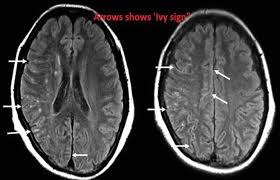

모야모야병은 뇌 기저부에 있는 주요 혈관이 점차 좁아지면서 뇌로 가는 혈류량이 줄어드는 질환입니다. 혈류가 부족해지면 뇌는 새로 가늘고 약한 혈관을 만들어 혈류를 보완하려고 하는데, 이 혈관들이 모여 있는 모습이 연기처럼 보여 ‘모야모야’라는 이름이 붙었습니다.